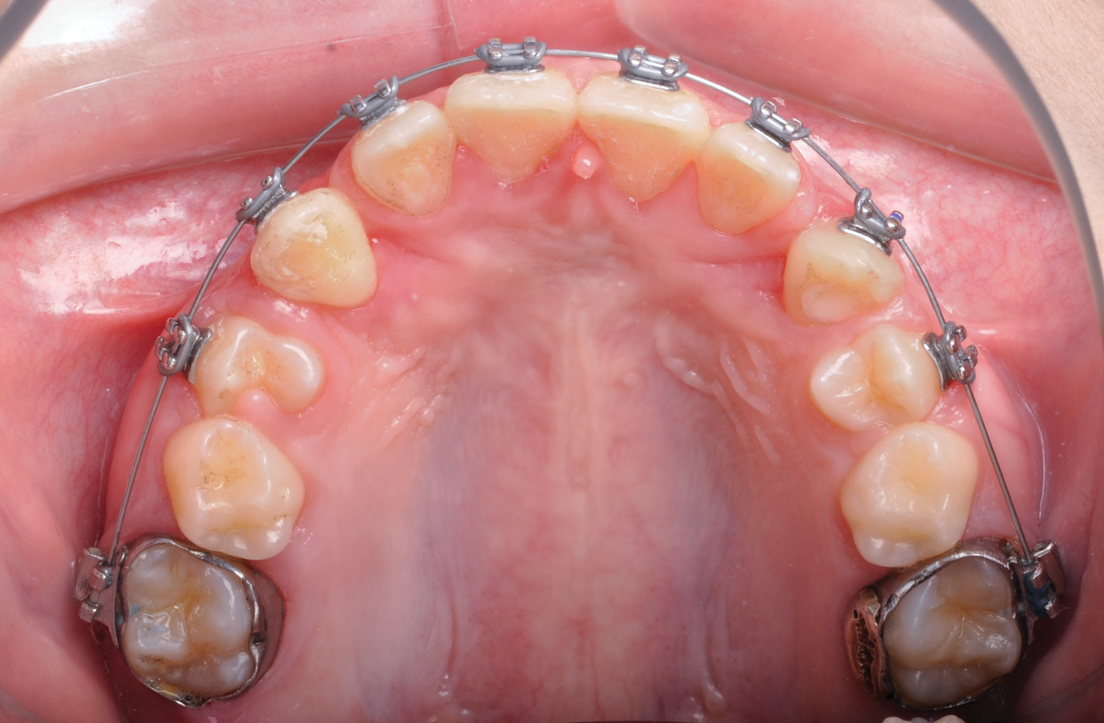

Fig 6. Use of apically positioned flap to manage bilateral facially impacted canines. During the same procedure a midline frenectomy was performed after the exposure and bilateral brackets were placed (Fig 6). Orthodontic traction was performed, which allowed both canines to be properly placed in the upper arch (Fig 7).

Figure 6

Fig 7. Use of apically positioned flap to manage bilateral facially impacted canines. During the same procedure a midline frenectomy was performed after the exposure and bilateral brackets were placed (Fig 6). Orthodontic traction was performed, which allowed both canines to be properly placed in the upper arch (Fig 7).

Figure 7